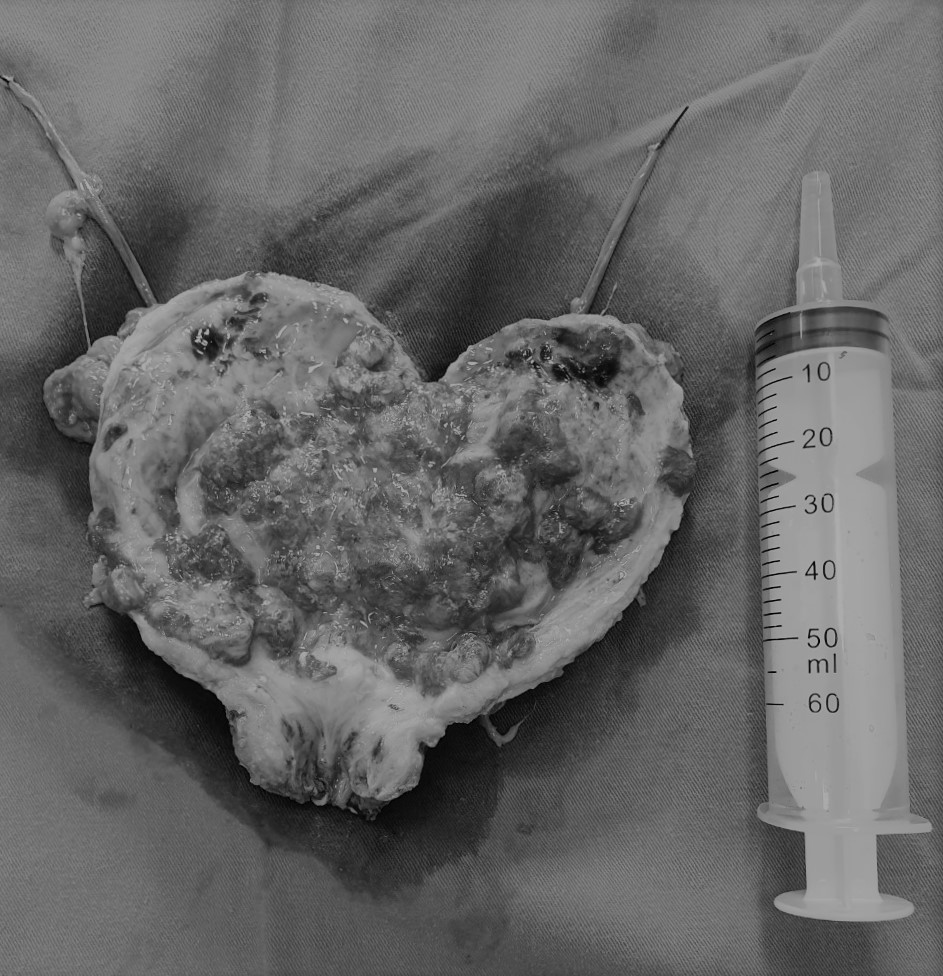

Đứng trước bệnh nhân có tình trạng bệnh lý nặng kèm nhiều bệnh phối hợp như: suy thận, tăng huyết áp, đái tháo đường type 2, có nhiều polyp trực tràng, các bác sĩ Khoa Ngoại thận tiết niệu – Nam học, Bệnh viện đa khoa Quốc tế Hải Phòng quyết định phẫu thuật cắt toàn bộ bàng quang, túi tinh, tuyến tiền liệt, nạo vét hạch 2 bên, chuyển lưu nước tiểu theo phương pháp Bricker nhằm điều trị triệt căn ung thư, nâng cao chất lượng sống cho bệnh nhân. Ca phẫu thuật kéo dài 6 giờ đồng hồ được thực hiện thành công, sau mổ bệnh nhân tỉnh táo, tình trạng sức khỏe tiến triển tốt, ung thư được triệt căn hoàn toàn.

Phẫu thuật cắt toàn bộ bàng quang, chuyển lưu nước tiểu theo phương pháp Bricker là một trong những phẫu thuật đặc biệt khó, chuyên sâu trong phẫu thuật tiết niệu, được chỉ định cho bệnh nhân ung thư bàng quang sâu, xâm lấn, không còn chỉ định phẫu thuật nội soi. Việc cắt bỏ toàn bộ bàng quang, nạo vét hạch rộng rãi nhằm điều trị triệt căn ung thư, từ đó ngăn chặn nguy cơ tái phát, phát triển khối ung thư mới, hạn chế việc phải dùng hóa trị, xạ trị với bệnh nhân, kéo dài thời gian sống. Phẫu thuật này đòi hỏi phải được tiến hành ở bệnh viện có trang thiết bị y tế hiện đại, đội ngũ phẫu thuật viên giàu kinh nghiệm, trình độ chuyên môn vững vàng để kiểm soát tốt các tai biến trong và sau mổ như chảy máu, nhiễm khuẩn vết mổ, nhiễm khuẩn đường niệu, tắc ống thông để dẫn lưu niệu quản, tắc ruột, dính ruột…